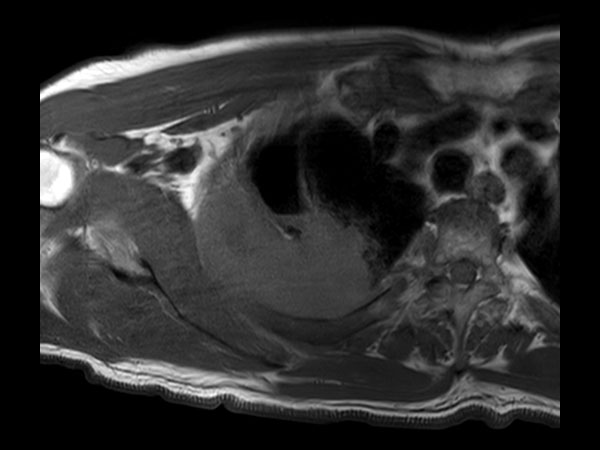

Axial T2w mDIXON XD TSE (Water only)